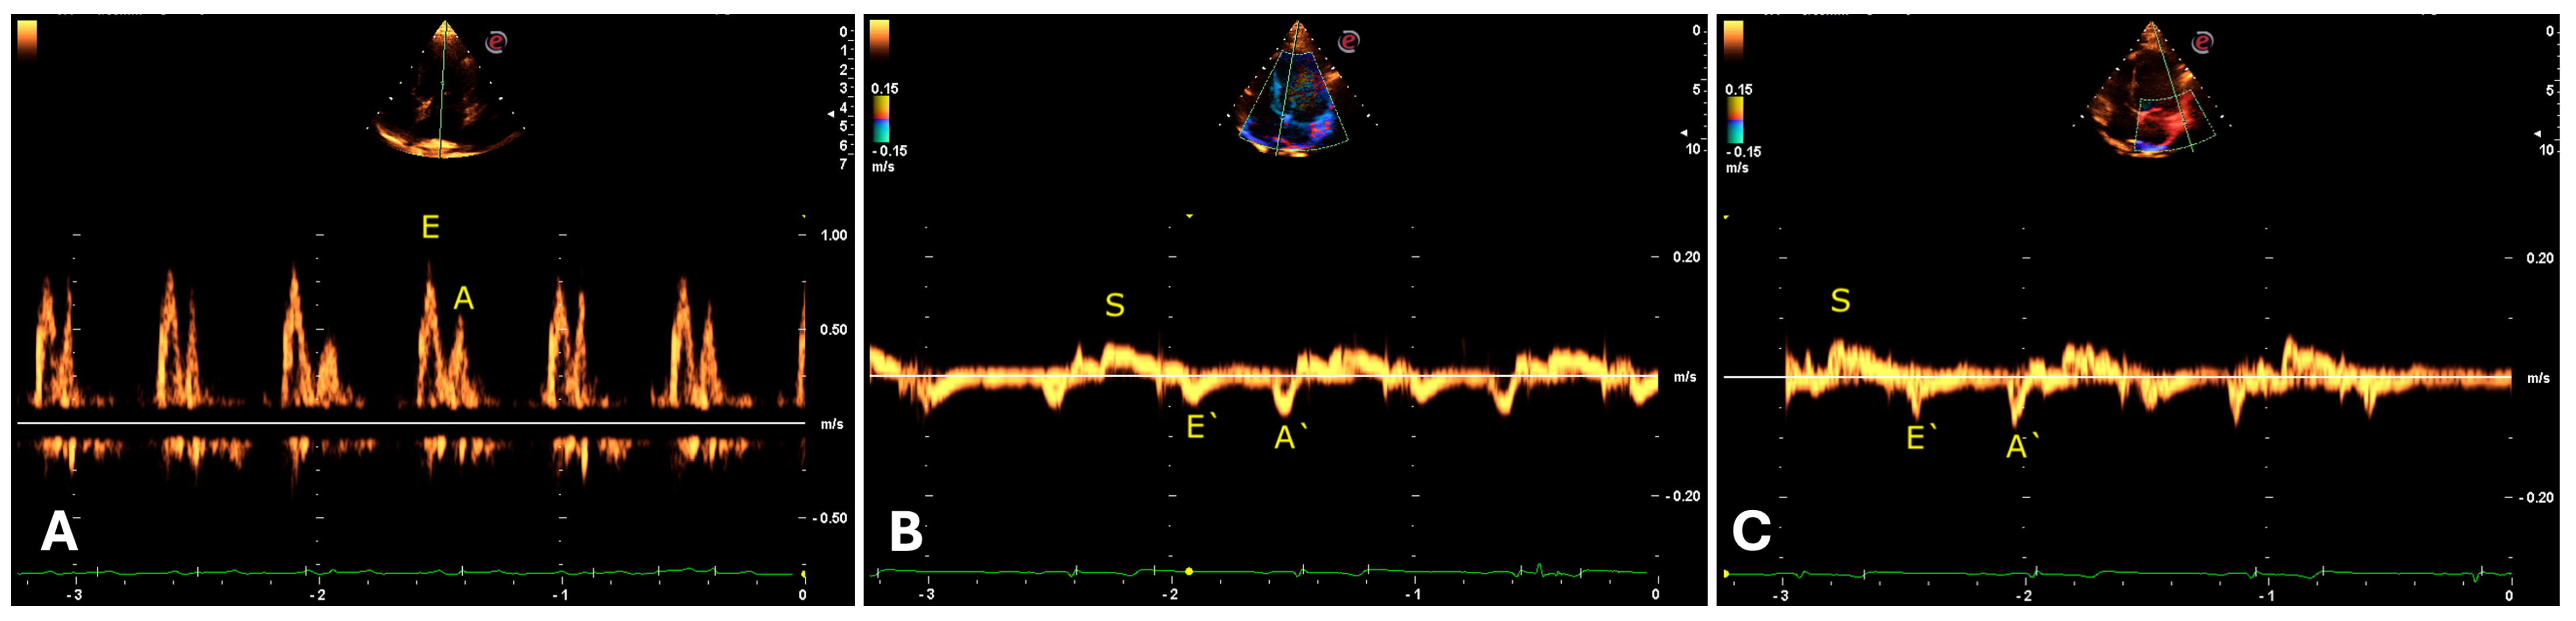

Regarding the transmitral flow measured by the pulsed Doppler method, an E wave pattern with greater amplitude than the A wave was identified (Table 8). In the evaluation of the mitral septal and parietal valve annuli using tissue Doppler, an E’ wave pattern smaller than A’ was observed, suggesting an abnormal type II (pseudonormal) ventricular filling pattern (Figure 8). The same patterns were observed in the right chambers (Table 9).

Data obtained from pulsed Doppler in transmitral flow (E and A) and tissue Doppler in the septal and parietal valve annulus of the left and right ventricles (E’ and A’) exhibited an abnormal type II (pseudonormal) ventricular filling pattern differing from healthy and non-anesthetized domestic species [29]. This finding may be related to the anesthetic protocol’s effect, resulting in a longer E wave deceleration time (DT) in the echocardiogram, inversely proportional to heart rate, in addition to increased ventricular filling pressures observed in transmitral flow. Carvalho et al. (2019) documented similar results in domestic cats subjected to continuous dexmedetomidine infusion.

Figure 8. Evaluation of transmitral flow by pulsed Doppler in a four-chamber apical window indicating E and A waves (A). Tissue Doppler evaluation of the mitral annulus from apical images indicating inversion of E’ and A’ waves in the septal (B) and lateral (C) regions in jaguars anesthetized with medetomidine and ketamine. S = Systole.